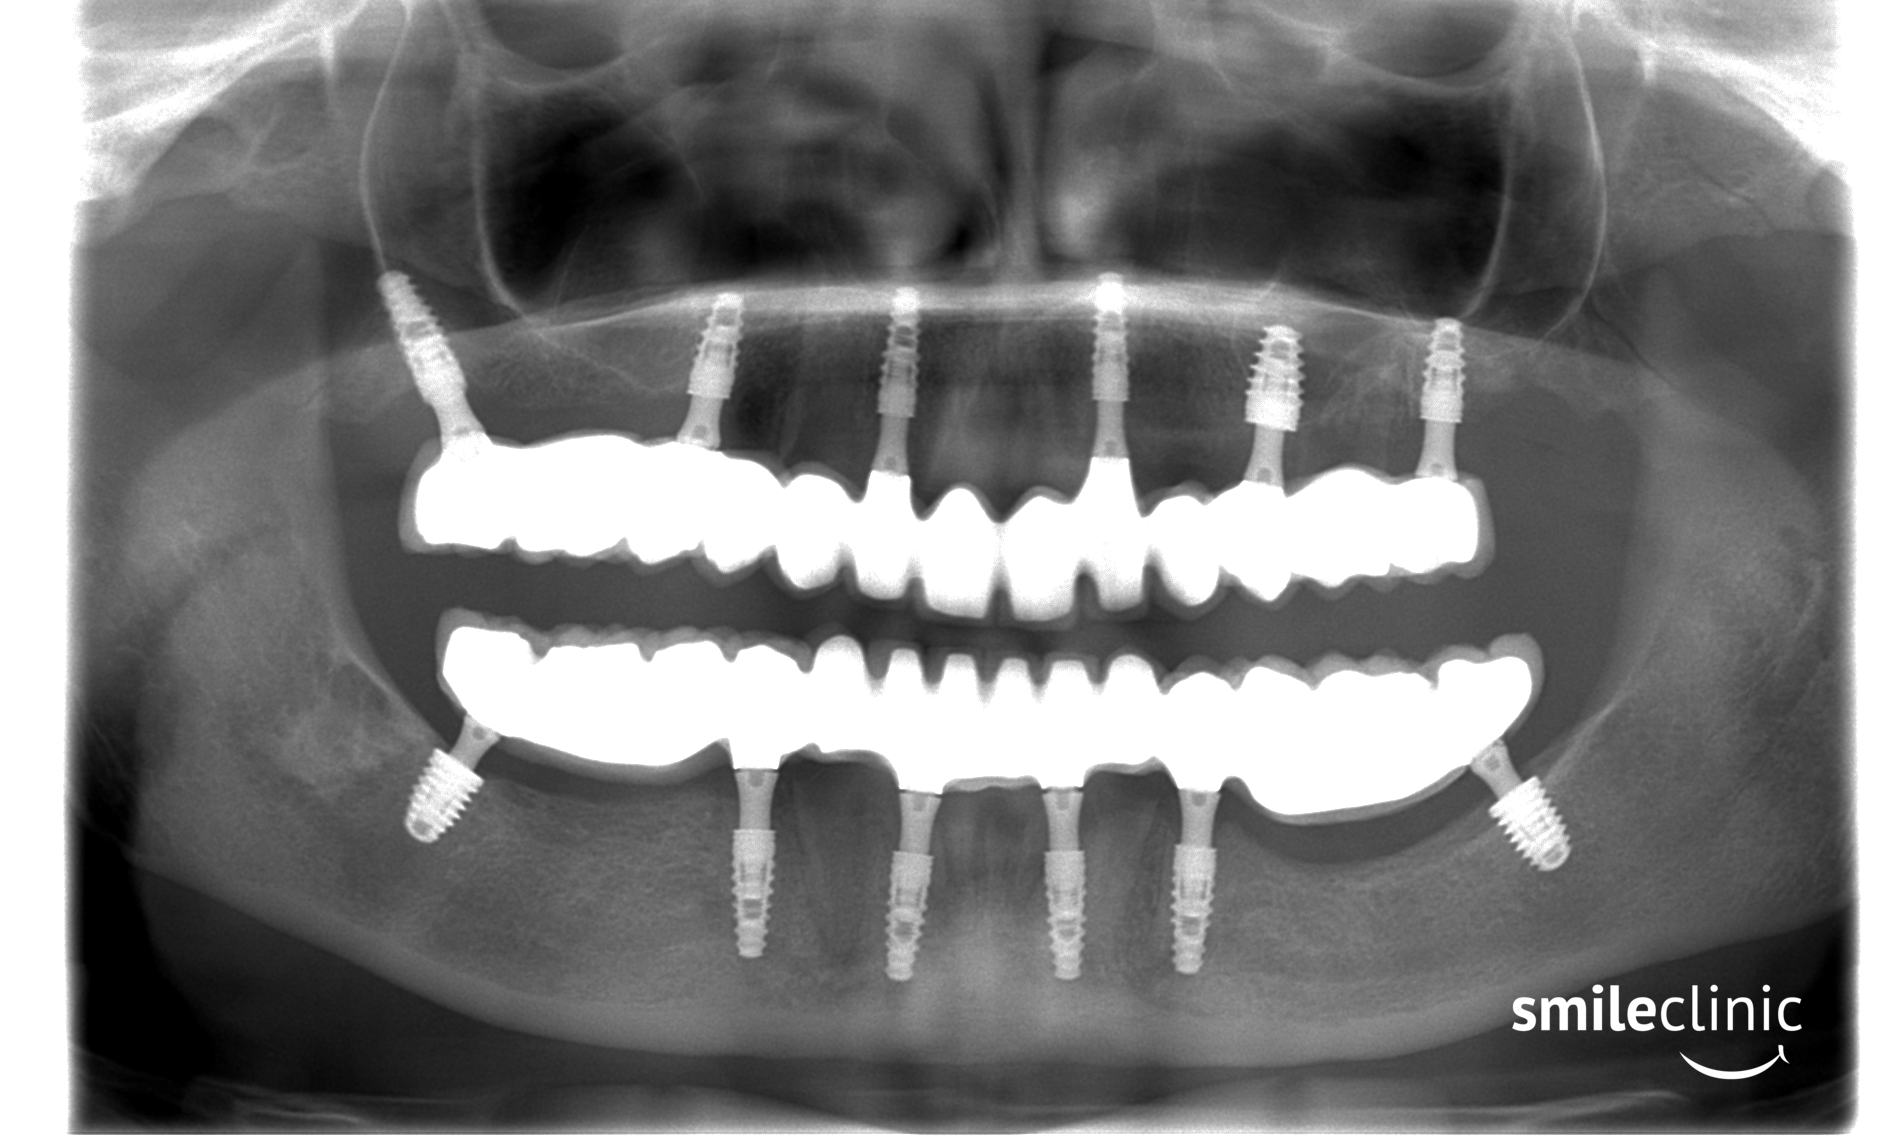

This patient recieved All on 5 procedure on both her jaws. As you can see in the X-ray taken after the treatment, she now has 5 dental implants in her lower and 5 dental implants in her upper jaw. On these implants is placed a fixed 14-point bridge.